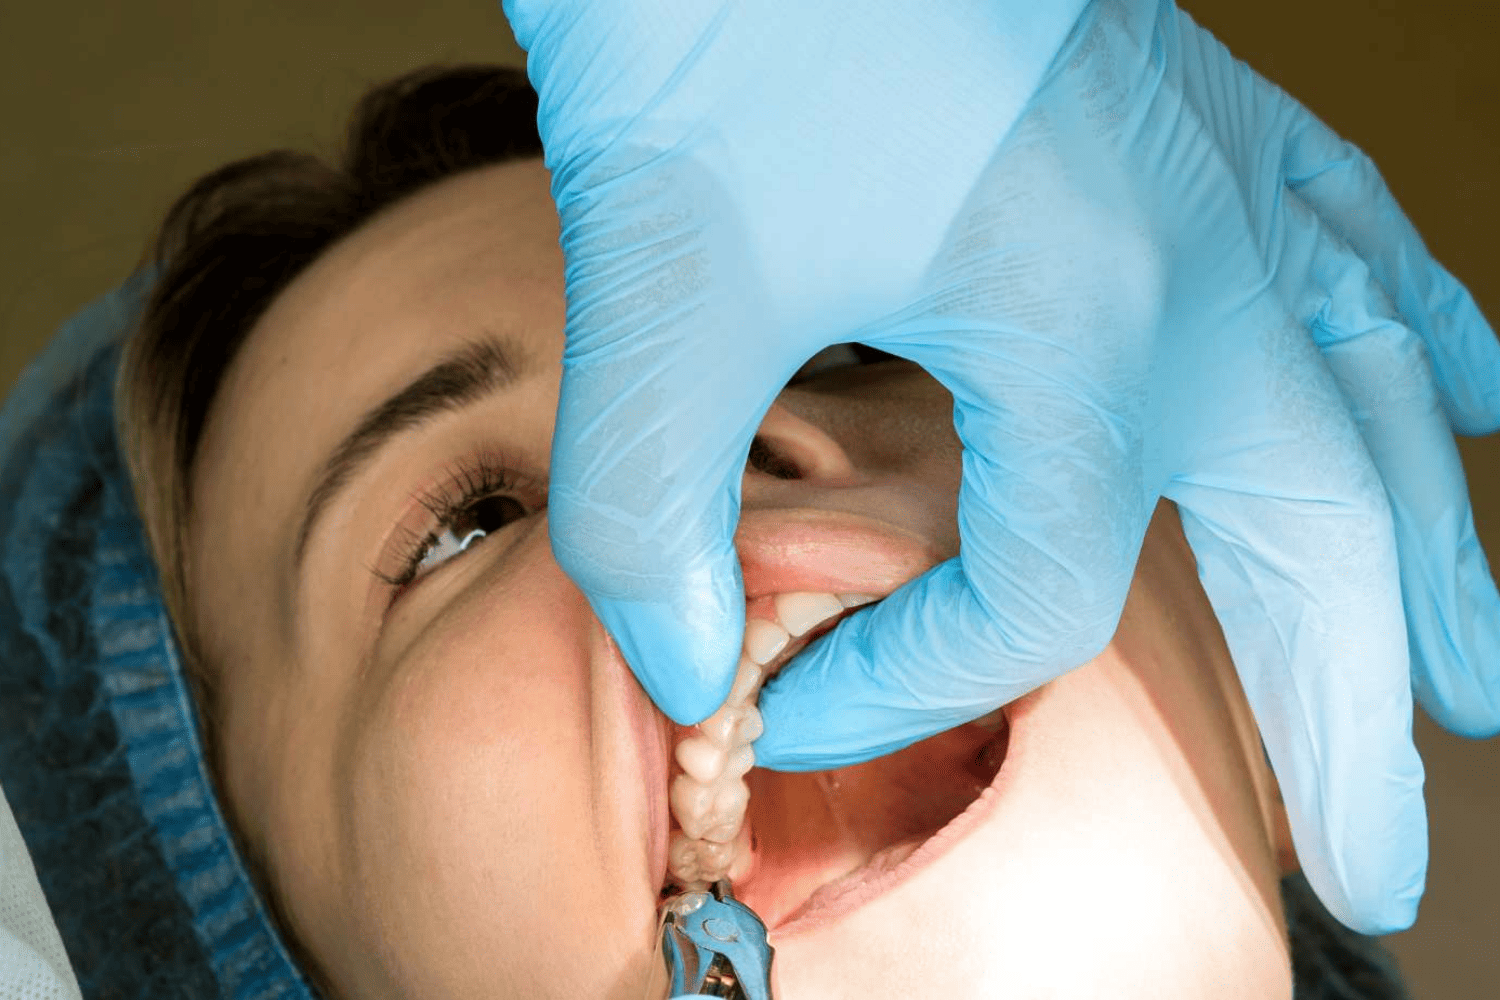

READ MORETeeth Extraction Services Crowns Bridges Dentures Teeth Cleaning...

READ MOREWisdom Tooth Extraction Services Crowns Bridges Dentures Teeth...